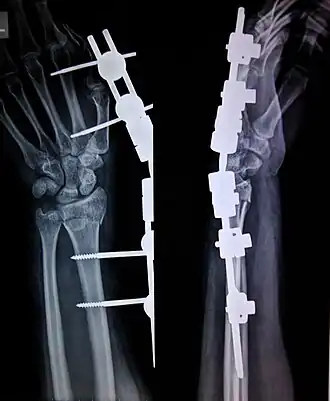

External fixation is a surgical treatment wherein Kirschner pins and wires are inserted and affixed into bone and then exit the body to be attached to an external apparatus composed of rings and threaded rods — the Ilizarov apparatus, the Taylor Spatial Frame, and the Octopod External Fixator — which immobilises the damaged limb to facilitate healing.[1] As an alternative to internal fixation, wherein bone-stabilising mechanical components are surgically emplaced in the body of the patient, external fixation is used to stabilize bone tissues and soft tissues at a distance from the site of the injury.

In this kind of reduction, holes are drilled into uninjured areas of bones around the fracture and special bolts or wires are screwed into the holes. Outside the body, a rod or a curved piece of metal with special ball-and-socket joints joins the bolts to make a rigid support. The fracture can be set in the proper anatomical configuration by adjusting the ball-and-socket joints. Since the bolts pierce the skin, proper cleaning to prevent infection at the site of surgery must be performed.

The parts of an external fixator include:

- Schanz pin

- Connecting rods

- Clamps